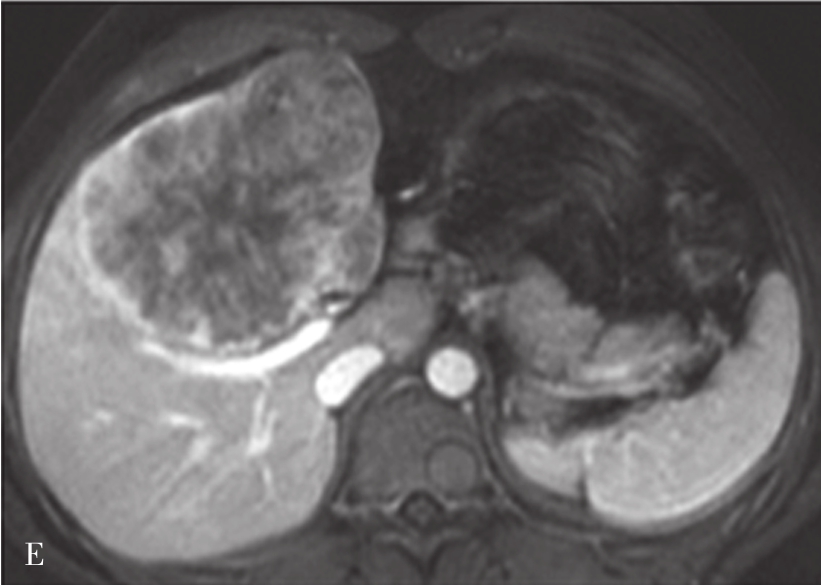

A.CT平扫图像,肝右前叶内可见巨块状稍低密度影,大小约10.5cm×8.3cm,CT值为36~46HU,其内密度不均,界限欠清,病灶内可见更低密度影;B.增强扫描动脉期,病灶不均匀强化,CT值约69HU,并见多量小刷状不成熟肿瘤血管影(箭头);C.增强扫描门脉期图像,病灶密度略低于肝脏实质,CT值约68HU,病灶假包膜厚薄不均(箭头);D.3min延迟期图像,随着时间的延长,病灶密度低于肝脏实质,CT值64HU,中央低密度区未见明显强化;E.动脉期最大密度投影法重建图像示肝动脉分支明显增多供应病灶

图5-21-42 HCC患者的MRI图像

A.T 2 WI脂肪抑制图像,可见肝右前叶内较大略高信号为主的病灶,内有点状更高信号影及中央低信号区,边界较清楚;B.600s/mm 2 时DWI图像,可见病灶为略高信号为主,中央略低信号;C.脂肪抑制图像,可见病灶为低信号影,边界较清楚,其内有一高信号影(箭头),为出血信号;D.增强扫描动脉期图像,可见病灶内轻微强化;E.可见门脉期图像病灶不均匀强化;F.可见延迟期图像病灶大部强化,中央无强化,假包膜清楚

HCC最常见的MRI表现为T 1 WI呈略低信号,T 2 WI呈略高信号,DWI呈高信号(图5-21-42)。有文献报道T 1 WI呈等信号者,多为分化较好的早期HCC,而脂肪变、出血、坏死、细胞内糖原沉积或铜沉积可导致病灶在T 1 WI上呈高信号,此外,在肝血色病基础上发生的HCC,由于肝实质在各脉冲序列图像上信号均很低,病灶一般都呈相对高信号。肿瘤假包膜可见于40%~70%的结节型和巨块型HCC。Gd-DTPA增强较为特征性的强化形式是对比剂“快进快出”,其原理为这些病灶70%的血供来自肝动脉,延迟相上出现宽0.5~3mm的包膜强化也颇具特征。采用特异性肝细胞摄取的对比剂,比如钆塞酸二钠(Gd-EOB-DTPA,普美显)不仅有其他钆类对比剂同样的动态增强外,在静脉注射10~30min内约有50%被正常肝细胞摄取,而不含正常肝细胞的HCC则很少或基本不摄取,而在肝特异性期呈低信号。有助于小HCC与肝硬化再生结节和其他良性病变的鉴别。大多数HCC在肝特异性期呈现相对低信号,但约10%的分化程度较好的HCC亦可呈等或高信号。